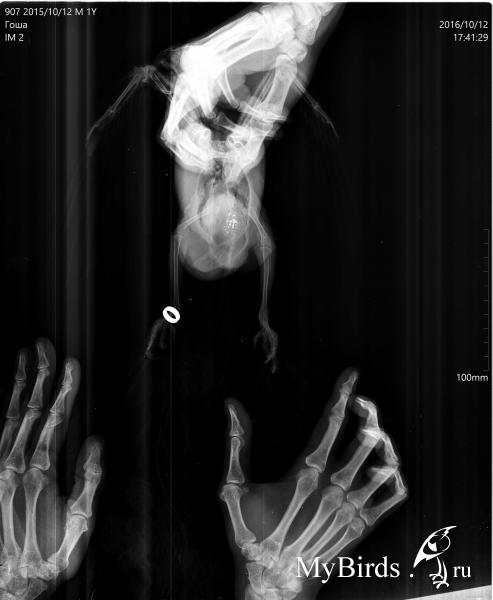

zima543 Опубликовано 12 октября, 2016 Автор #17 Опубликовано 12 октября, 2016 Тут как смогла пыталась сфоткать образование. Оно достаточно большое, с залысиной. Вроде серого цвета. Растекаемости по жердочке не заметила. Помет не видела, видимо, клетку только помыли. Глазки чистые, клоаку не увидела. Птиц дичится. Но не кричит, просто отходит (если так можно сказать о какаду в кенаровской клетульке). Попискивает. Не кричал.Плохо перенес рентген. Там кричал и извивался. Прошу, посмотрите, пожалуйста. Время до принятия решения до завтра. Иначе птицу продадут..

KamaRo Опубликовано 12 октября, 2016 #22 Опубликовано 12 октября, 2016 zima543, снимки очень плохие. На форуме есть статья о рентгене, http://www.mybirds.ru/health/rentgen.phpИ прежде, чем ехать нужно дома потренироваться в раскладке и фиксации.Вот еще статья и примеры как должен выглядеть снимок, http://www.vetruno.ru/articles/?item=67 Вот какими должны быть фото опухоли, http://www.mybirds.ru/forums/index.php?s=&...t&p=1181717 (хотите/не хотите, а нужно собрать волю в кулак, птицу зафиксировать в руках, перо намочить, щеточкой расчесать и в макрорежиме хорошего качества фотографировать).Или вот так, http://www.mybirds.ru/forums/index.php?act...t&id=407436Вот смотрибельное фото липомы, http://www.mybirds.ru/forums/index.php?act...t&id=407464На счет "птица дичится" - это всего лишь трудности. Если хотите какие то рекомендации нужны хорошие фото (читабельные) и читабельный рентген.

zima543 Опубликовано 12 октября, 2016 Автор #23 Опубликовано 12 октября, 2016 Птица не моя. Рентген по моей огромной просьбе делали в лучшей ветклинике города. Я читала как правильно делать рентген. Если хоть какой то шанс понять по этим фото? Больше мне птицу никто не даст для еще одного рентгена. Неужели, все зря?

KamaRo Опубликовано 12 октября, 2016 #24 Опубликовано 12 октября, 2016 Клинка может быть хорошей, но если разложили птицу неправильно и также зафиксировали, то рентген не прочесть.Птица перекошена, часть закрыто рукой. Я поэтому ссылку на статью Маркиной дала - на снимках птицы разных размеров, поп снимкам как будто одного (еще и рентген аппарат настроили, чтобы мелкая птица занимала весь снимок.Окончательный вердикт вынесет Зося, может Александр Томашевский зайдет в тему и тоже свое мнение скажет.Если на нем ничего не прочтут - да, свозили птицу зря и деньги потратили тоже. По фото нет шансов что то понять. Какие должны быть фото я вам ссылки дала.